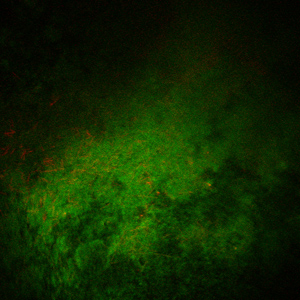

Characterize biofilm formation by Cl. difficile in vitro and in vivo by culturing and fluorescent in situ hybridization (FISH) imaging methods.